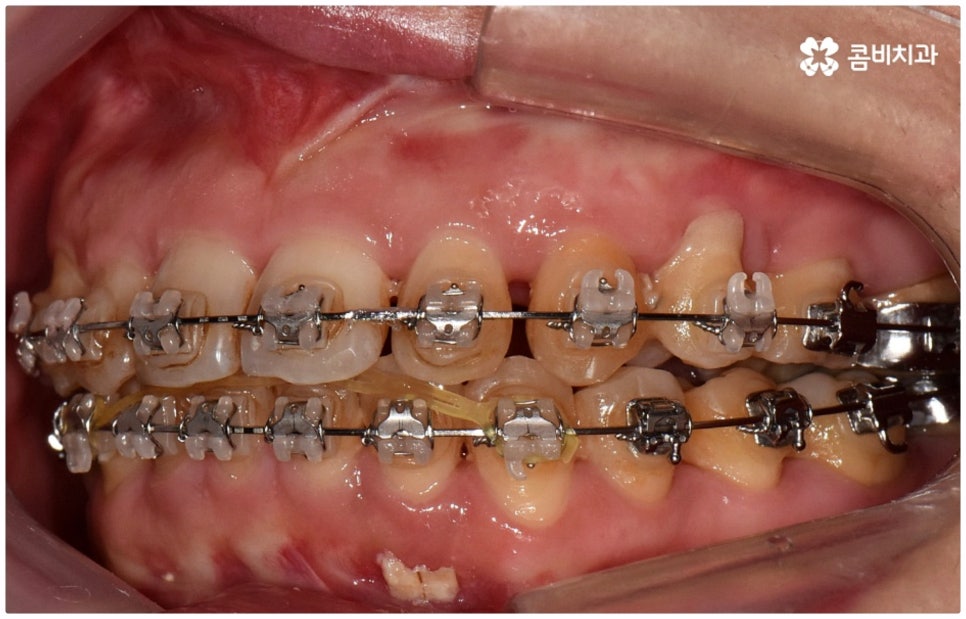

출처 아카이브 열기위아래 치열이 제대로 맞물리지 않으면 음식물을 씹을 때 어려움을 느끼거나 발음상 문제가 생길 수 있습니다. 이것을 부정교합이라고 하며, 그 종류는 상악과 하악의 골격적인 전후방 관계를 기준으로 1급, 2급, 3급으로 나눌 수 있어요. 위아래 어금니는 잘 맞물리는데 치열이 조금씩 삐뚤어져 있거나 치아 사이가 벌어져 있는 등 살짝씩 어긋난 부정교합은 1급, 위 어금니가 더 앞으로 나가있는 부정교합은 2급 (ex. 돌출입), 그리고 아래 어금니가 더 앞으로 나가있는 부정교합은 3급 (ex. 주걱턱) 으로 분류하게 되는데 이 중 오늘 살펴보려고 하는 것은 부정교합 3급에 해당하는 반대교합에 대한 거예요.

정상적인 교합은 윗 앞니가 아래 앞니를 살짝 덮는 정도로 윗니가 조금 더 앞으로 나와 있으면서 위아래 치아가 어금니까지 잘 맞물리는 것을 말하는데 반대교합은 위아래 앞니가 거꾸로 물리는 증상을 보이기 때문에 저작 활동 및 발음 조성이 원활하지 않게 되며 반대교합교정 등 적절한 치료를 받지 않고 방치할 경우 점점 더 주걱턱이 강화되는 쪽으로 뼈가 성장할 수 있어 될 수 있는 대로 빠른 시일 내에 원인을 분명하게 알아보고 그에 맞는 치료를 받는 것이 중요하다고 할 수 있어요.

골격적인 원인이 아니라면 위턱과 아래턱의 위치나 크기에는 이상이 없는데 치아의 맹출 각도 및 방향의 문제로 인해 치아가 반대로 맞물리게 된 치성 반대교합에 해당하는 경우라고 할 수 있는데요. 그 원인으로는 선천적인 치열의 문제 (아래턱 앞니 치축이 앞으로 기울거나 위턱 앞니 치축이 뒤로 들어감), 유치가 너무 빨리 빠지고 영구치가 자리를 제대로 잡지 못해 생긴 문제, 후천적인 습관 (혀를 내밀거나 손톱을 깨무는 등 치열에 좋지 않은 영향을 주는 행위를 지속적으로 반복) 으로 인한 문제 등등을 살펴볼 수 있으며, 보통 이런 경우 앞니 4~6개 치아 일부에 국한된 문제이기 때문에 보다 빠르고 간단하게 교정 치료가 가능하므로 꼭 성장기에 치료를 시작하지 않고 성인이 된 후라고 해도 비교적 쉽게 개선이 될 수 있습니다.

교정 치료가 생물학적 반응을 이용하는 것이다 보니 성장기에 진행하면 치아 이동 및 회복 속도 등에 장점이 있는 것은 분명하지만 그렇다고 해서 성인 이후 중장년 분들이 교정 치료를 받을 수 없는 것은 아니며 이미 많은 분들이 도움을 받고 계신 만큼 이에 대해서 한 번 고려해 보시면 좋을 거예요. 혹시 성장기 이후로는 양악 수술 등으로만 치료가 가능한 것이 아닐까 생각하셔서 부담스럽게 느끼셨던 분들이라면 지레 겁을 먹고 불편함을 그대로 방치하시기 보다는 검진 및 상담을 통해 적극적으로 이를 해결해 보시길 권유드리고 있어요.

물론 원인과 정도에 따라 외과적인 방법이 필요하신 분들도 있을 수 있지만 교정을 통해 얼마든지 치료가 가능한 경우도 있으며 앞서 말씀드렸던 것처럼 발전된 교정 기술 및 특수 미니스크류 등의 장치 개발을 통해 턱의 방향을 조금씩 회전시켜 원거리 치아 이동을 유발하는 것이 가능해졌기 때문에 예전에는 한계가 있었던 부정교합 케이스도 개선될 여지가 늘어나고 있습니다. 꼼꼼하게 검진을 받으시고 자신의 상황에 맞는 교정 치료를 무리하지 않게 진행하신 후 철저하게 사후 관리를 해주시면 보다 오랜 기간 동안 건강하게 고른 치열을 유지하면서 생활하실 수 있을 거예요.